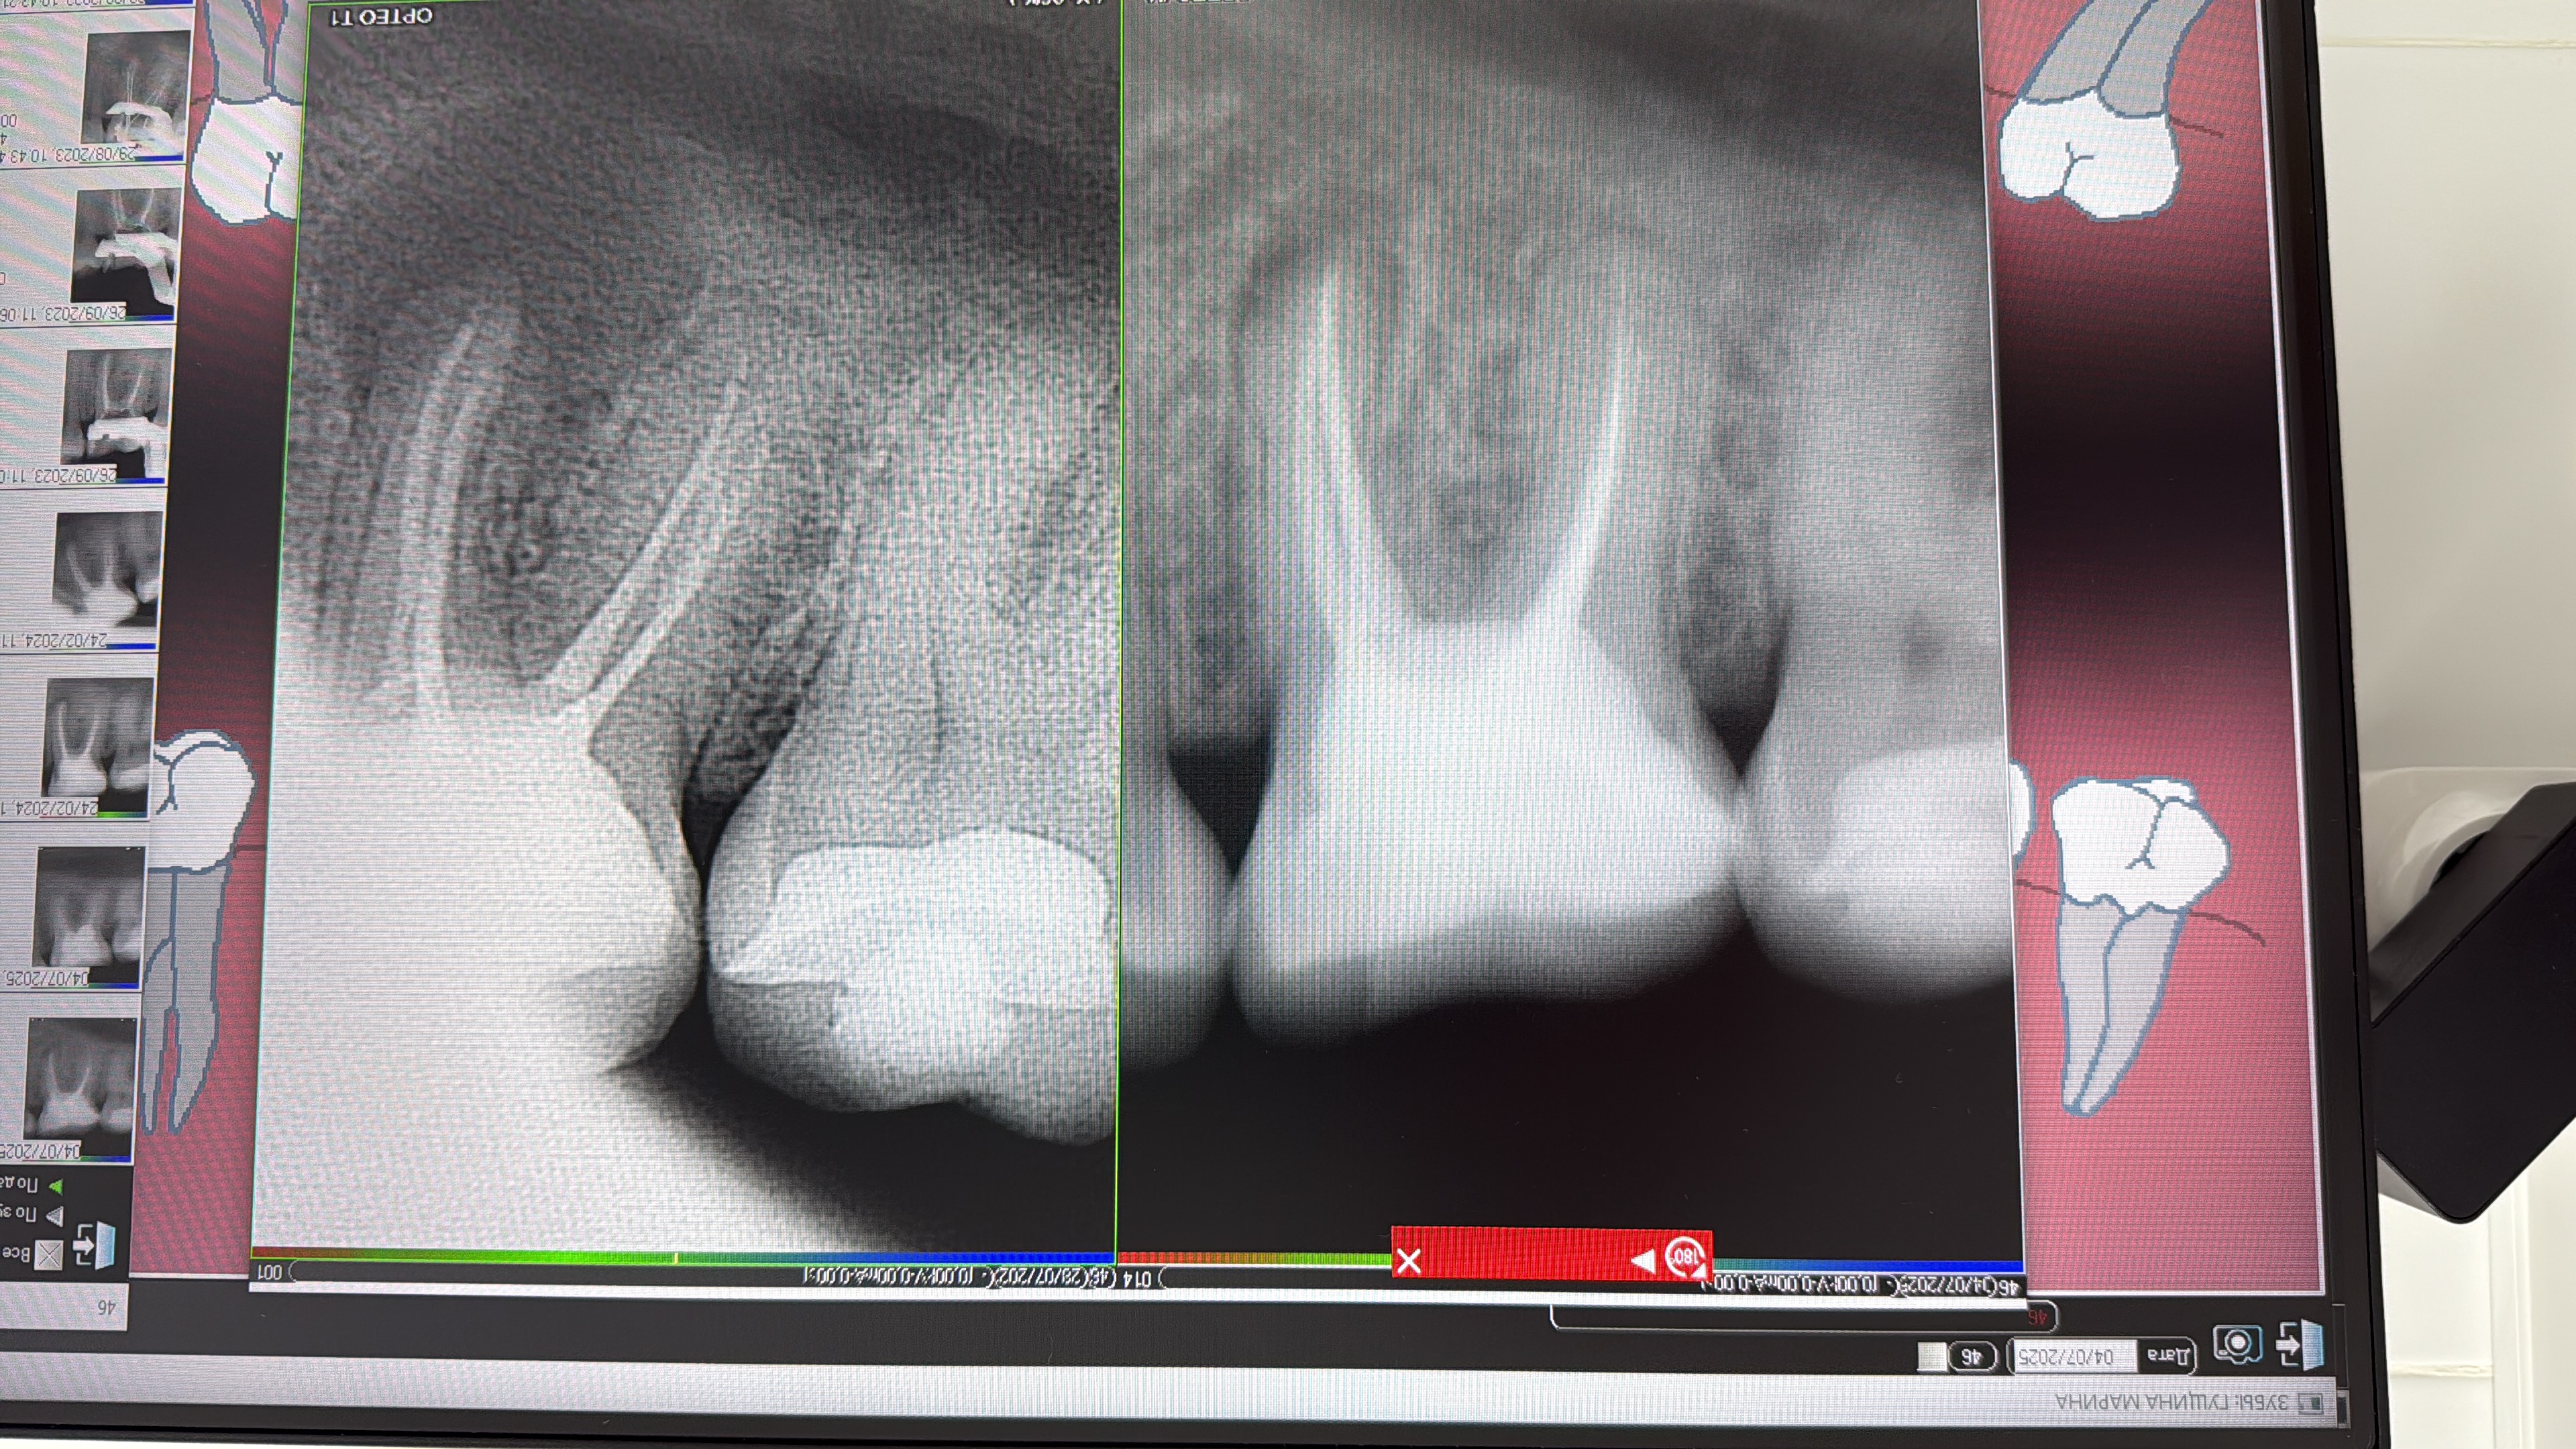

- Проведение полной профессиональной консультации по здоровью зубочелюстной системы, составление комплексного плана лечения, рекомендации по поддержанию качественной гигиены полости рта, обучение правильной технике чистки зубов, анализ снимков на визиографе и рентген-аппарате, анализ Клкт снимков

- Владение современными методиками пломбирования корневых каналов, обработки и распломбировки многокорневых зубов любой степени сложности